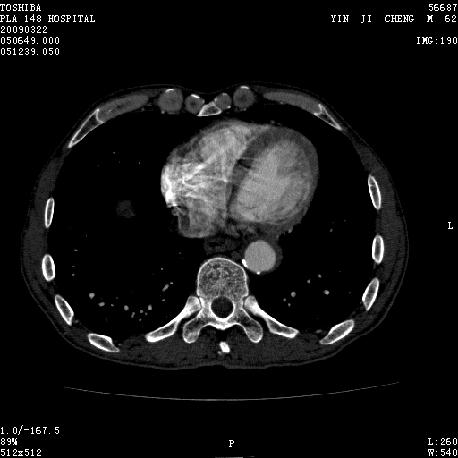

男 62 夜间突然腹痛并向背部放射 ,急诊疑胰腺炎 ,胰淀粉酶正常 ,ct示胰腺未见明显异常,发现降主动脉密度欠均,做主动脉造影示胸腹主动脉半月形低密度充盈缺损,内膜钙化并内移,累及腹腔干致根部明显狭窄,未见明显破裂口。 本人为是不典型夹层,其他人有说是动脉硬化或动脉炎的。请大家发表一下看法。

可惜图像太小,但结合病人年龄、病史及降主动脉壁增厚及模糊表现应该考虑,在我看到的急性主动脉夹层别人中血管壁都有这样改变。

主动脉附壁血栓?主动脉夹层?

我觉得这个不像主动脉夹层,应该是血栓多点,如果可以重建个mpr也许对诊断更有帮助。